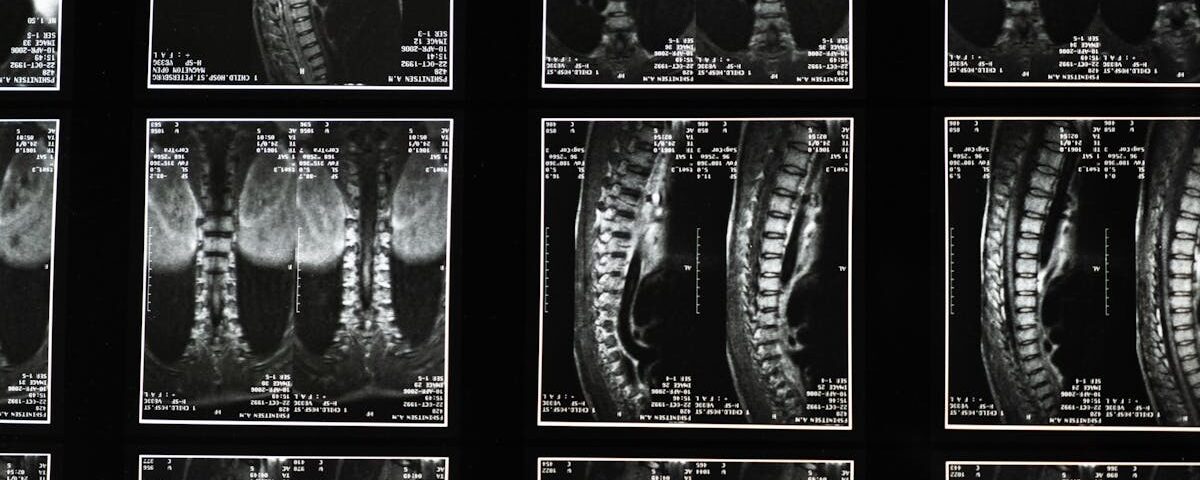

Technologie Modernes

Imagerie médicale, applications de suivi de santé.